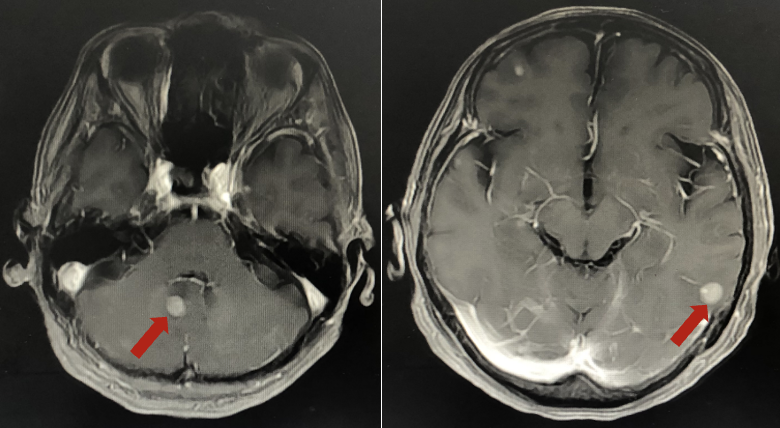

2024年5月头颅增强MR:脑内多发异常强化灶,较前增多增大。

三线治疗方案:T-DXd (200mg 体重37kg 5.4mg/kg)(依据DESTINY-Breast系列研究)。

疗效评估:疾病进展(PD)

2024年8月头颅增强MR:脑内多发异常强化灶,较前增多增大,进展。

三线PFS:3个月

三线进展时基于DESTINY-Breast系列研究,换用T-DXd(德曲妥珠单抗)是非常合理的选择,但患者耐受性差,需优化支持治疗或调整剂量。